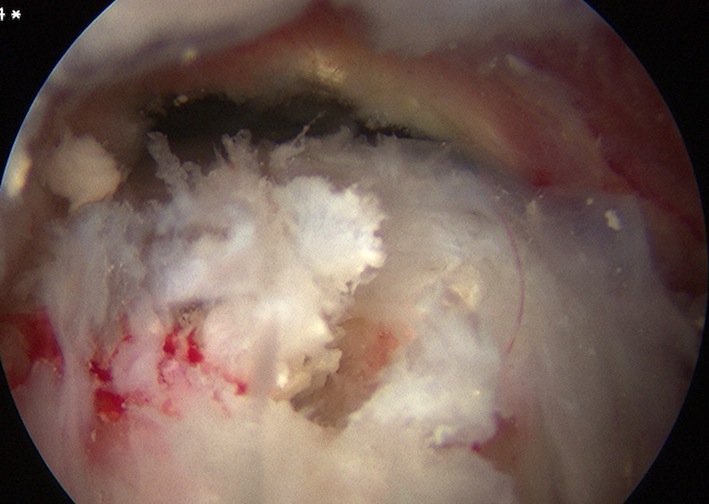

Calcium IncisionCalcium in TendonCalcific Tendonitis Arthroscopy 4

Longitudinal incision of rotator cuff / debridement of calcium / rotator cuff repair